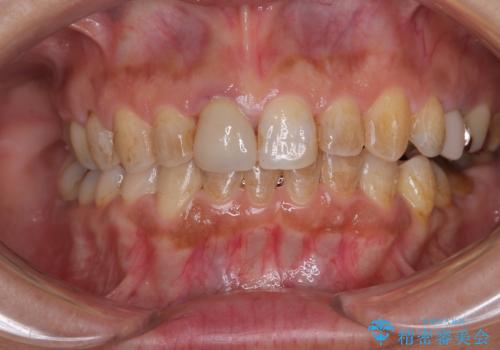

- 上下前歯のデコボコと、治療途中の歯を気にして来院された患者様です。

ご家族がインビザラインにて矯正治療を行っていたため、ご本人の希望によりインビザラインによるマウスピース矯正を行うこととしました。

根管治療が必要な歯は事前に処置を行った上で矯正治療を開始し、概ね歯列が整ったところでセラミッククラウンなどに置き換え、その後インビザラインを1セット使用して仕上げていくこととしました。